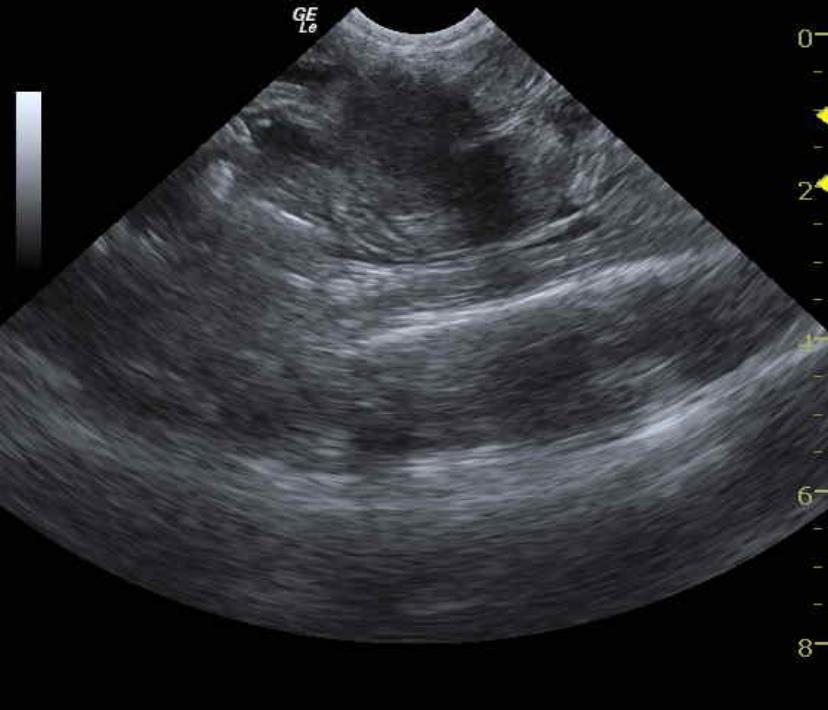

Image Interpretation

The abdomen in this patient presented a mild amount of echogenic fluid. Aggressive medullary rim sign was present in the kidneys suggestive of FIP or emerging lymphoma. Mesenteric root lymphadenopathy was also noted and dramatically hypoechoic.